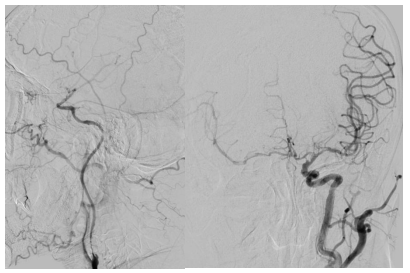

第二步,处理动脉瘤,拆除不定时炸弹。医生将微导管超选择进入动脉瘤腔内,依次填入数枚弹簧圈,直至动脉瘤完全栓塞,不再显影。因为动脉瘤瘤颈宽,故于载瘤动脉内植入了支架以达到致密栓塞,降低复发率。

第三步,解除狭窄,恢复血流。选择合适尺寸的球囊扩张式支架,精准释放于右侧椎动脉起始部狭窄段。

第四步,最终验证。再次造影显示:狭窄消失,支架位置良好。动脉瘤不显影,弹簧圈致密填塞。